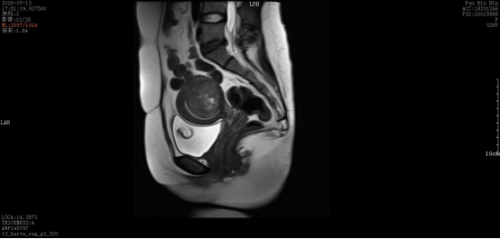

术前:

微波消融后肌瘤病灶内会发生凝固性坏死,即刻超声造影就可以看到病灶内没有造影剂充填。磁共振增强扫描病灶内呈现充盈缺损,增强后呈黑色区域,表示病灶坏死区域。坏死的病灶随时间推移,会逐渐萎缩吸收,子宫体积也会有一定的缩小,从而使痛经、月经量多等临床症状得到缓解和改善。